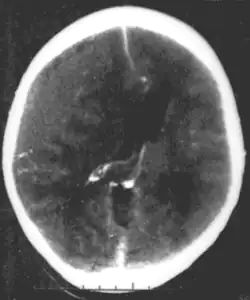

| Epidural hematoma, an example of a focal injury |

- Epidural hemorrhage is bleeding between the dura mater and the skull.[4] It is commonly associated with damage to the middle meningeal artery, often resulting from a skull fracture.